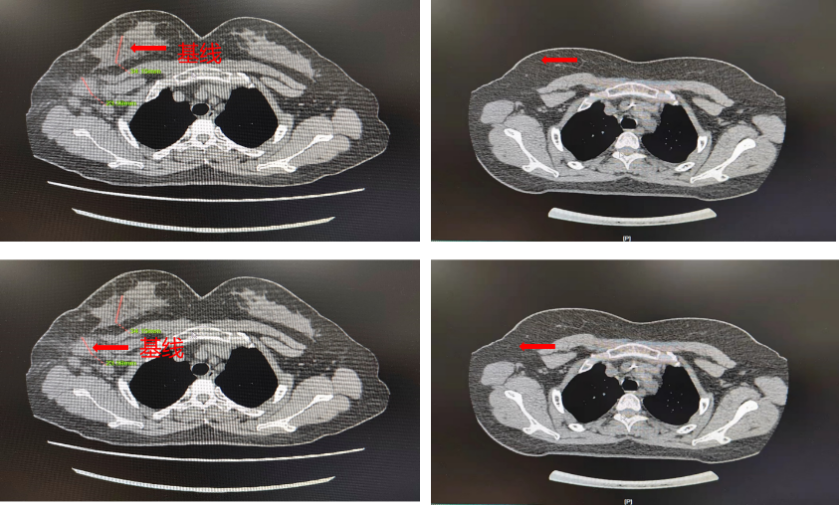

▌影像学评估(CT):

图4. 基线与6周期治疗后CT影像

该患者分别于2021-10-15、2021-11-5、2021-12-1、2021-12-22、2022-1-13、2022-2-8完成6周期新辅助化疗,方案:TCbHP,紫杉醇脂质体210mg+卡铂 0.6g+汉曲优(首次剂量 500mg,维持剂量380mg)+帕妥珠单抗(首次剂量 840mg,维持剂量420mg),该患者在完成第一周期新辅助化疗后,自觉肿块明显缩小,在行第3周期新辅助化疗入院后,予以完善乳腺MRI提示,乳腺肿物及腋窝淋巴结均明显缩小,查体几乎无法触及乳腺肿物及腋窝肿大淋巴结,继续完成6周期足量新辅助化疗后行乳腺癌改良根治术。